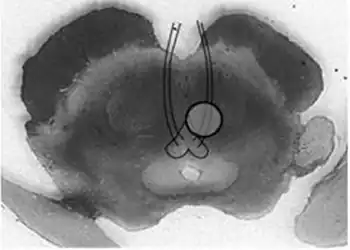

| Benedikt syndrome. Localization of oculomotor fascicle injury and symptoms of Benedkit syndrome. | |